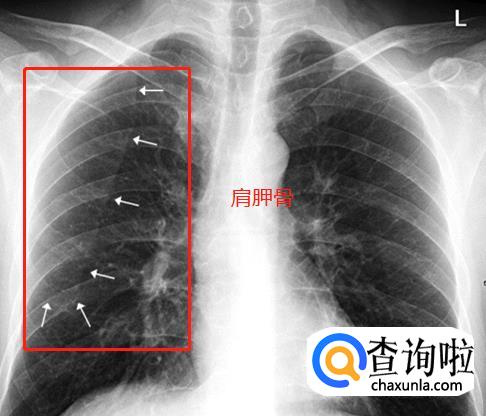

肩胛骨。如果投照时体位标准,上肢内旋充分,则肩胛骨应当位于肺野之外。否则肩胛骨将重叠于上肺野偏外的区域,呈与胸壁平行的条带状高密度影,此时可能会被误认为是肺内病变。仔细观察可见肩胛骨影从肺内向肺外延伸,即可与肺内病变区别。下图双上肢未充分内旋,导致双侧肩胛骨大部分重叠于双肺中上肺野中外带,导致相应肺野条带状密度增高。白色箭头标示右侧肩胛骨内侧缘,向肺外延续。左侧肩胛骨情况类似。